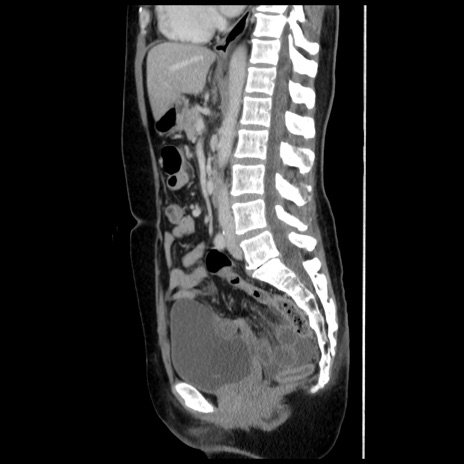

冠状断像